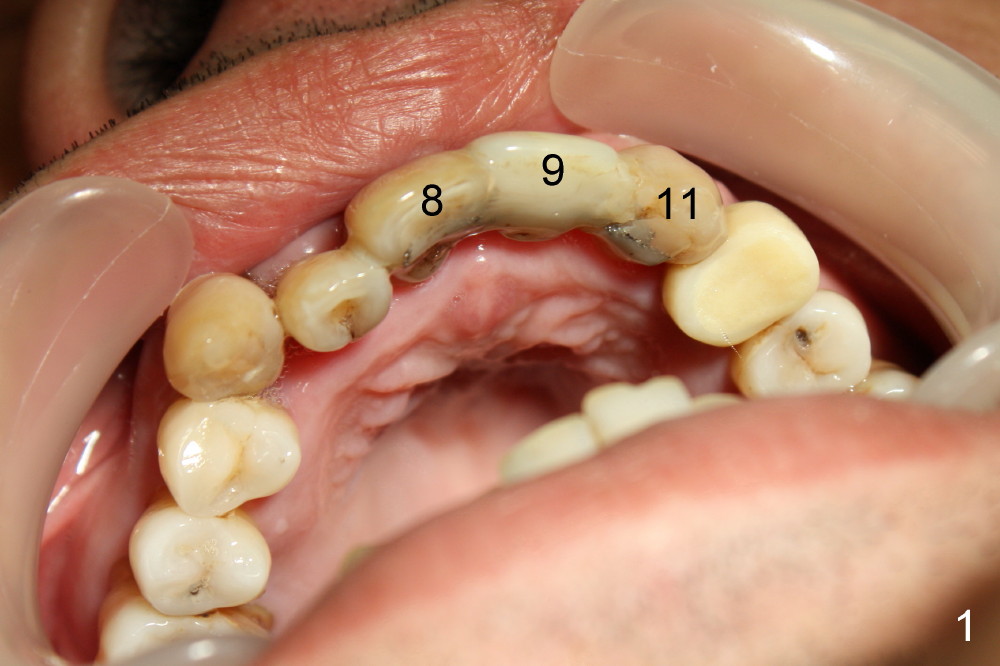

Removal of Two Mesiodens Followed by Immediate Implants and Provisionals

CBCT shows that the two mesiodens, esp. left one, are close to the palatal plate. After removal of the peridontally compromised tooth #8 and the pontic #9 (as compared to Fig.1), the palatal flap is raised to expose the left mesiodens (Fig.2 <; *: incisal foramen).

These two anterior implants remain stable 2 months 20 days postop, since one of the immediate provisionals has incisal chip (Fig.11 *) while both of them are splinted (<) to increase retention. There is no complain about paresthesia around the incisal papilla due to separation of the nasopalatine nerve. Mesiodens sockets disappear 7 months postop (Fig.13). There is no bone loss 2 years 9 months postop (Fig.14 panoramus) or 4 years 10 months postop (Fig.15,16 CT). The buccal gingiva is reddish and swollen with bleed on probing and history of pain 7 years post cementation (Fig.17). There is no bone loss in PA (Fig.18). The buccal plate at #9 is thinner than that at #8 4 years 10 months post cementation (Fig.19,20).